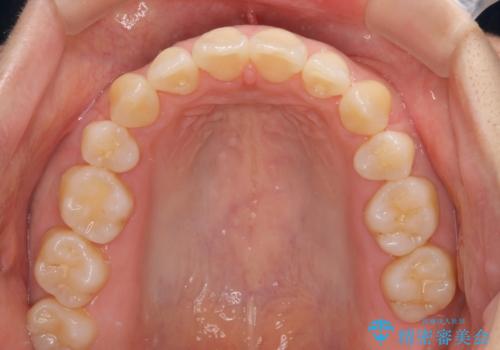

前歯のデコボコを抜歯矯正で改善 メタル装置で費用を抑える

- 治療期間

- 1年11ヶ月

もう少し口元の突出感を改善したかったのですが、舌の突出癖が影響し下顎前歯が唇側に押させる仕上がりとなりました。